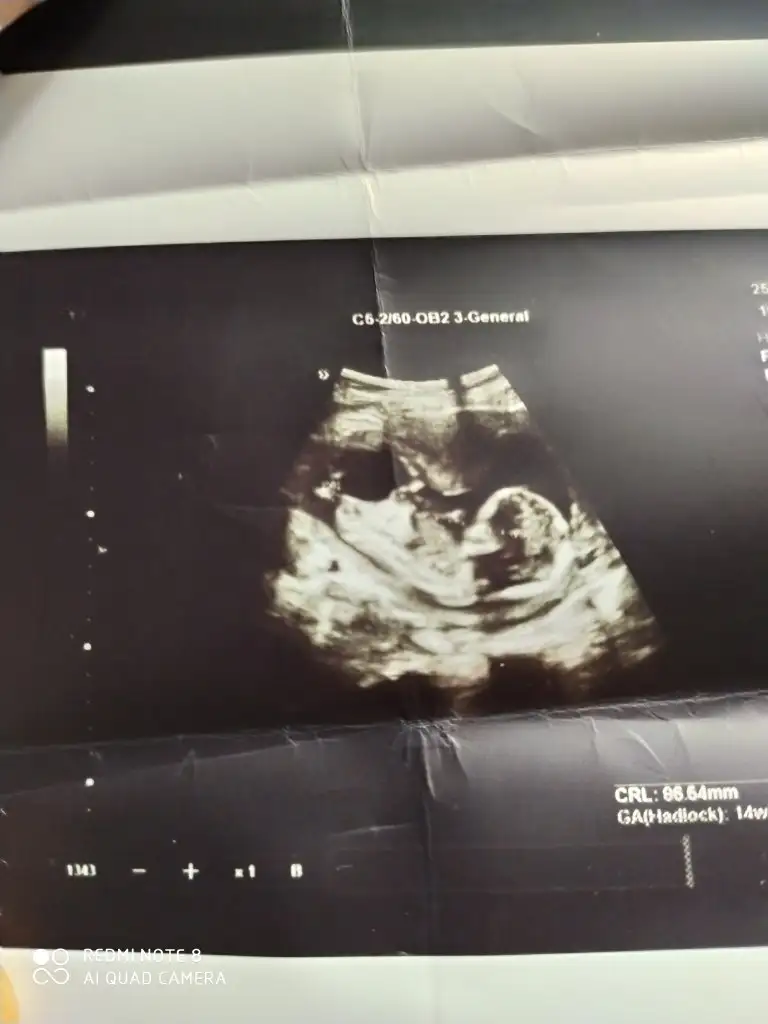

Bende bir kaç kişi diye baktırdım yorumları aynı bakalım sen ne diyeceksin kızkardeşimin 13 haftalık

13 haftalık doktor cinsiyeti söylemedi ama başkalarından tshmin aldim aynı cinsiyet i dediler bebek kardeşimin